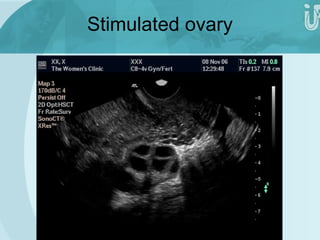

Stimulated ovary